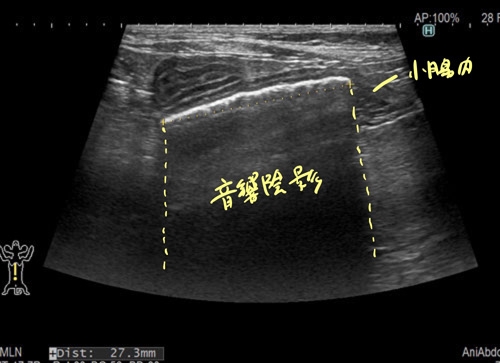

猫の小腸内異物(ジョイントマット)1 症例報告(高橋雅弘) 高橋ペットクリニック外科ケースより 猫の急性嘔吐と食欲不振 超音波検査において 小腸内に表面高エコーで音響陰影を伴っているため異物を疑います。 通過障害を疑う腸管の拡張が見られました。 以上の所見より小腸内異物と診断し、静脈内点滴を実施して緊急手術を行いました。 つづく!! « 前の記事へ カテゴリ一覧ページに戻る 次の記事へ »